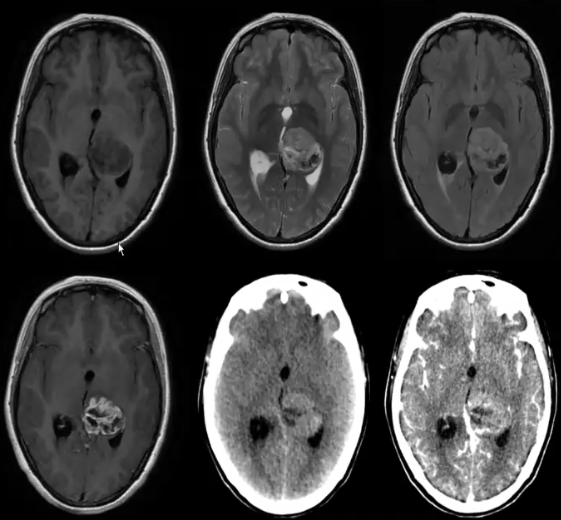

CT可见丘脑低、等混杂密度肿块,中心为低密度区,邻近侧脑室三角区内脉络丛钙化略向外移位,肿瘤边界多不清楚,密度不均匀,少数有钙化,周围可有水肿,增强扫描除儿童毛细胞型星形细胞瘤明显强化外,多数病例为环形增强或无增强。

MRI表现为丘脑区混杂信号肿块,T¹以低信号为主,间以等信号影,T2呈不均匀高信号,FLAIR亦呈不均匀高信号,其中肿块内坏死部分呈低信号,可有明显占位效应,强化特点与肿瘤分级有关,1-2级无强化或条片状强化,3-4级呈明显不规则环状强化。